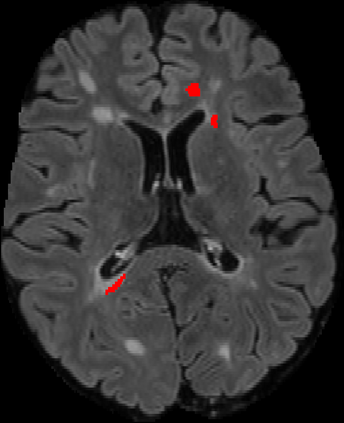

Assessment of lesions and their longitudinal progression from brain magnetic resonance (MR) images plays a crucial role in diagnosing and monitoring multiple sclerosis (MS). Machine learning models have demonstrated a great potential for automated MS lesion segmentation. Training such models typically requires large-scale high-quality datasets that are consistently annotated. However, MS imaging datasets are often small, segregated across multiple sites, with different formats (cross-sectional or longitudinal), and diverse annotation styles. This poses a significant challenge to train a unified MS lesion segmentation model. To tackle this challenge, we present SegHeD, a novel multi-dataset multi-task segmentation model that can incorporate heterogeneous data as input and perform all-lesion, new-lesion, as well as vanishing-lesion segmentation. Furthermore, we account for domain knowledge about MS lesions, incorporating longitudinal, spatial, and volumetric constraints into the segmentation model. SegHeD is assessed on five MS datasets and achieves a high performance in all, new, and vanishing-lesion segmentation, outperforming several state-of-the-art methods in this field.